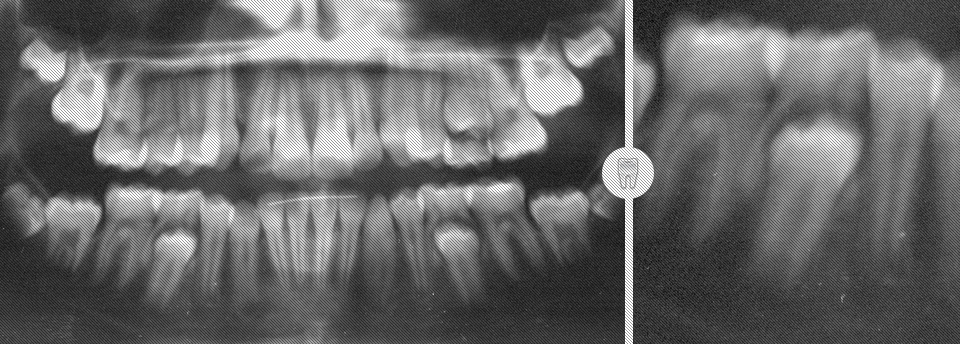

We enjoy working with children of all ages and feel it is very important to begin dental health early. Our patients are 3 years and up. Many dental problems can be intercepted and treated easily if diagnosed early. Our office offers sealants, fillings, crowns, extractions on “baby” teeth and adult teeth. We offer screening for future orthodontic treatment and have a wonderful team of specialists to help make difficult cases easy. Click here to find out more.